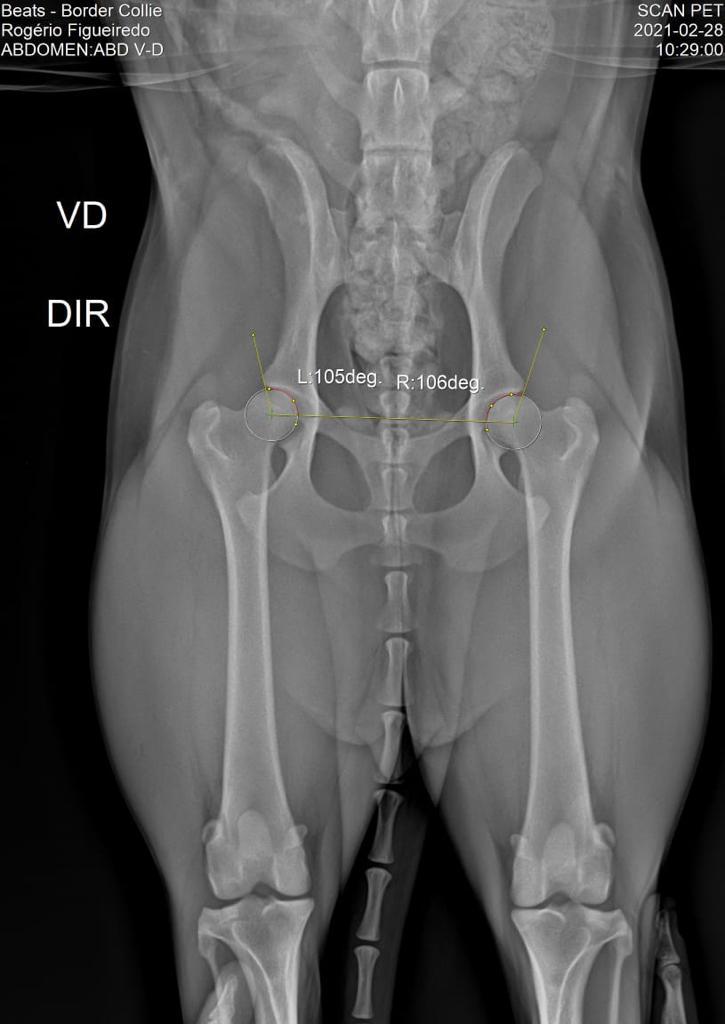

DISPLASIA

28/02/2021

ADEQUADO GRAU A

SCANPET

LAUDO

CHAPA